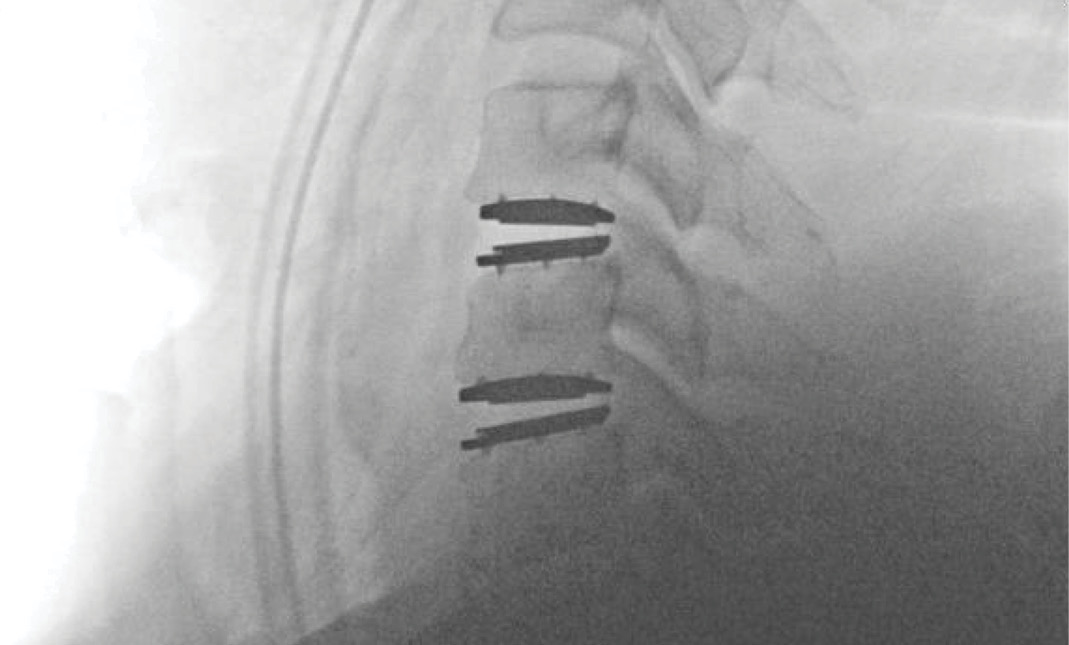

MRIs illustrated mild degenerative disc disease from C4-6 with disc herniations at both C4-5 and C5-6. The axial slice through C4-5 showed a right central disc herniation causing central and mainly right-sided foraminal stenosis. The axial slice through C5-6 showed a central disc herniation also causing central and mainly right-sided foraminal stenosis. The axial slice through C6-7 showed a left-sided disc herniation causing some left-sided foraminal stenosis, however, the patient did not demonstrate any left-sided symptoms.

Upon examination, the patient had good motion on flexion-extension, so fusion was not considered at all. My operative plan was to use prodisc cervical devices and replace both discs at C4-5 and C5-6, giving me the flexibility to use either a domed or flat implant.

During the procedure, prodisc C Vivo fit well within the C4-5 concave endplate. I expected to use a flat endplate prodisc C SK at C5-6, however I trialed the domed prodisc C Vivo and it actually looked good, so I unexpectedly used matching implants.